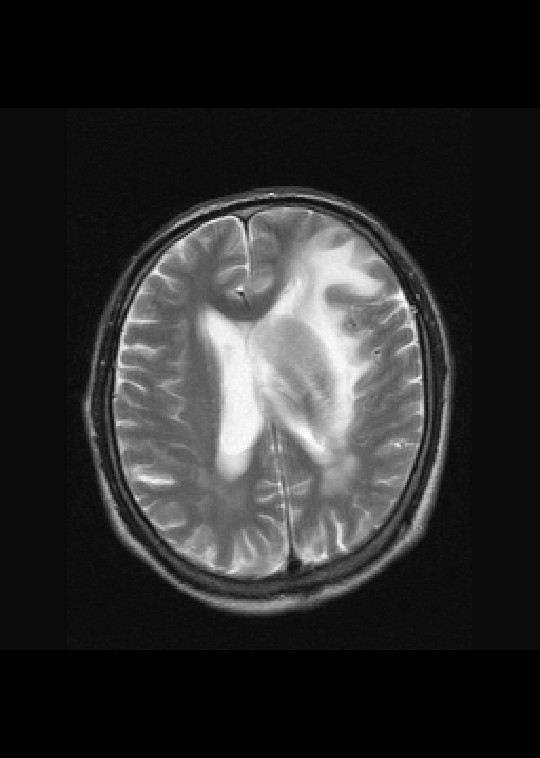

左侧基底节区病灶t1wi呈不均匀稍低信号,t2wi呈稍高信号,周围伴有水肿。增强扫描呈均匀团块样或者抱拳样明显强化,相邻的柔脑膜亦见线样强化。首先考虑淋巴瘤。可惜没有ct平扫,如果ct平扫病灶呈高密度,那么更支持pcnsl的诊断。

左侧基底节区长t1长t2异常团块状信号,增强呈明显均一强化,水肿明显,挤压侧脑室前脚,本人考虑为胶质瘤可能性大。

淋巴瘤可能性大,考虑侵犯侧脑室

左侧基底节区病灶t1wi呈不均匀稍低信号,t2wi呈稍高信号,周围伴有水肿。增强扫描呈均匀团块样或者抱拳样明显强化,首先考虑淋巴瘤。